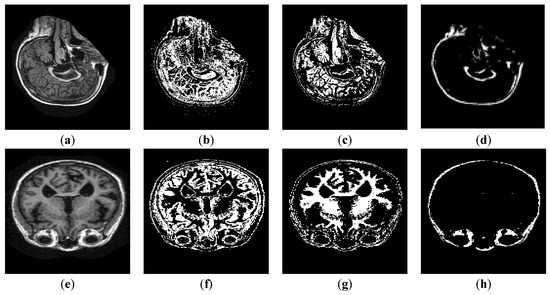

4.6.2. Segmentation Results

4.6.3. Layer-Wise Results of AlexNet